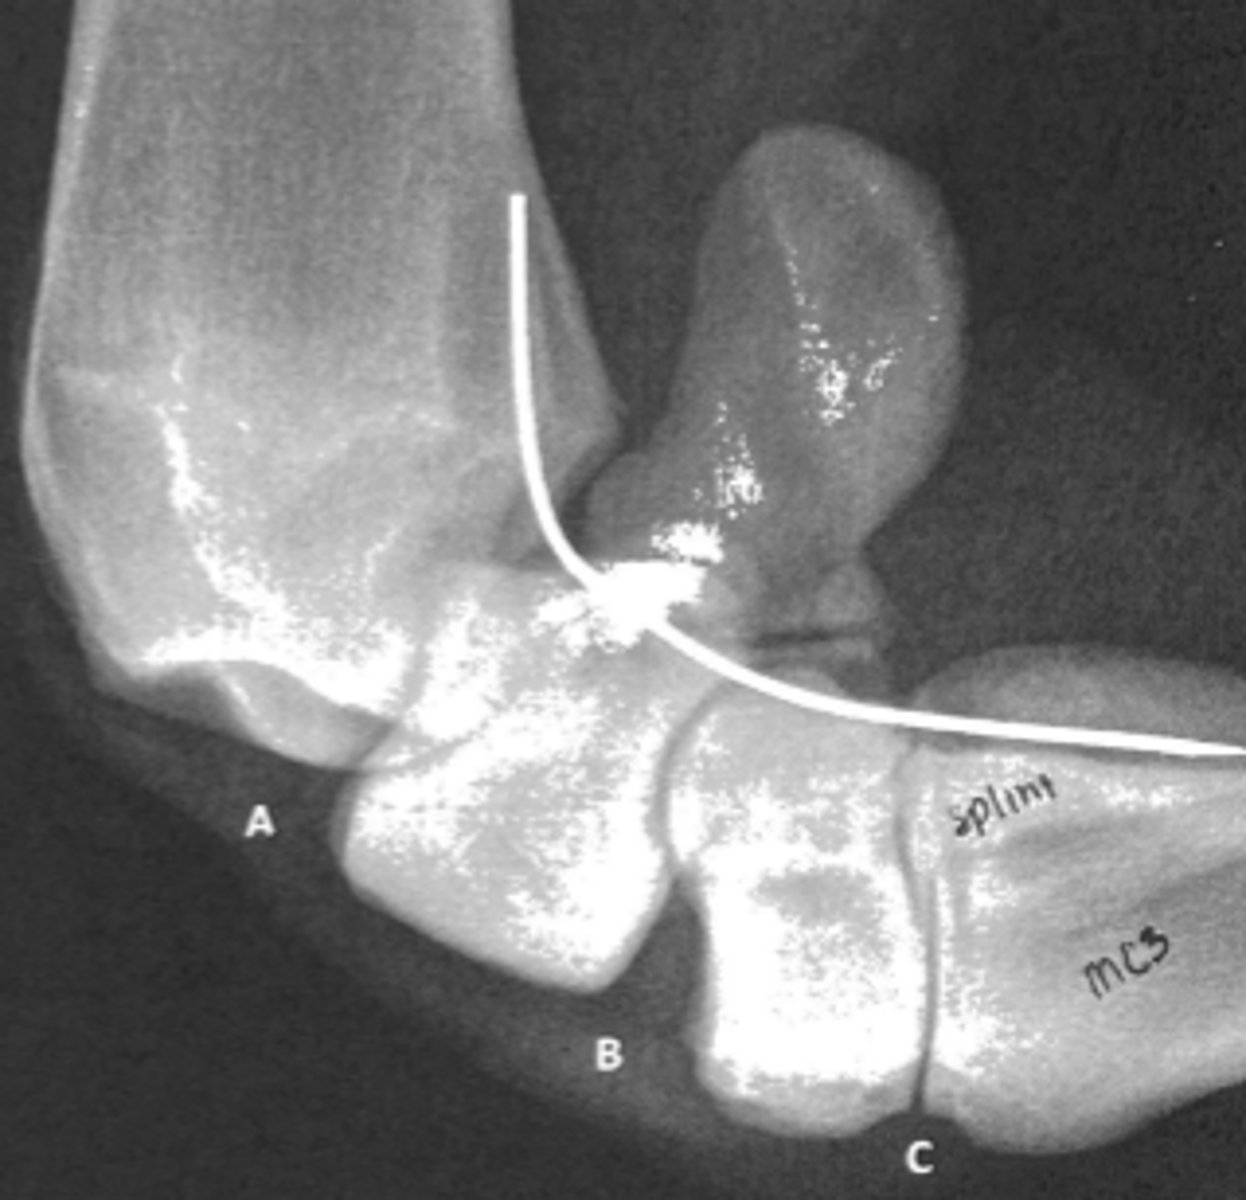

carpometacarpal joint

In this lateral radiograph, what is C?

B and C

Which joints communicate?

palmar carpal ligament

What structure is represented by the white line?